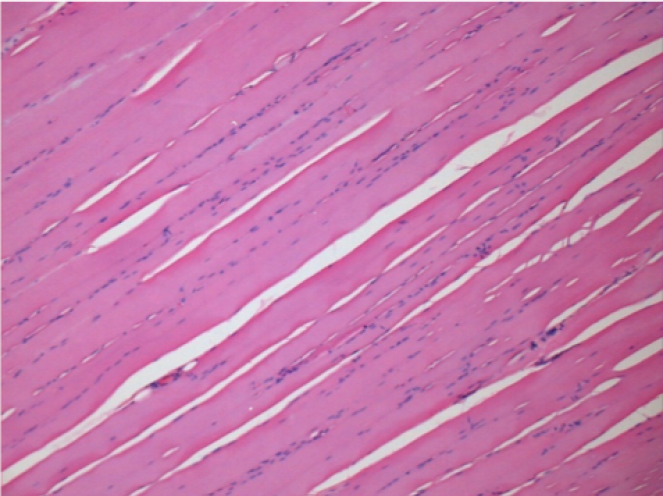

7 meses después de la inyección de Endopeel

7 meses (D210) después de la inyección IM de Endopeel 0,1 ml en el músculo pretibial derecho.

Restitutio ad integrum (restauración a la condición original) completa después de 7 meses

L : Control-100xD210

R:100xD210

L :Control 50xD210

R50X-D210